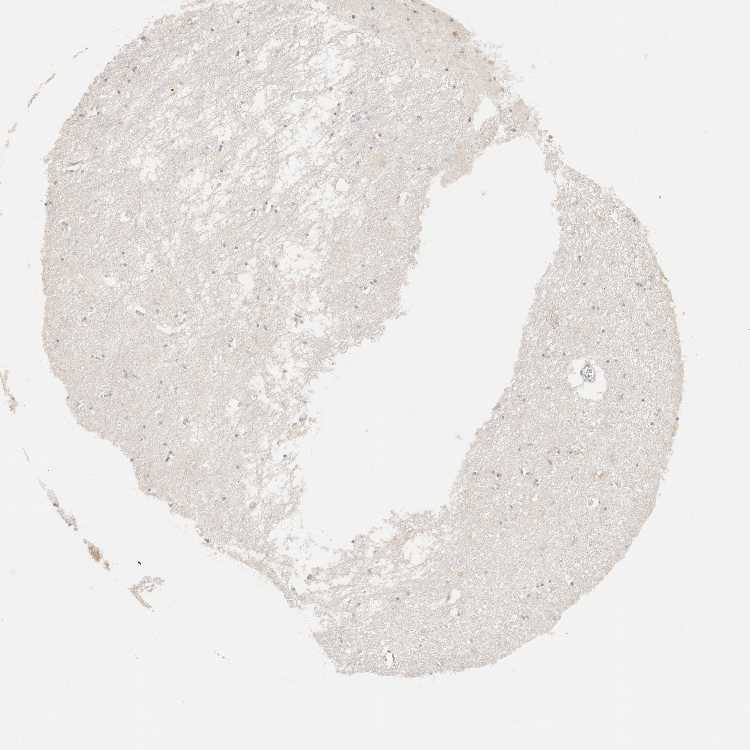

HIPPOCAMPUS - Antibody stainingi

Antibody staining in the annotated cell types in the current human tissue is reported as not detected, low, medium, or high, based on conventional immunohistochemistry profiling in selected tissues. This score is based on the combination of the staining intensity and fraction of stained cells.

Each image is clickable and will lead to virtual microscopy that enables deeper exploration of all samples and also displays staining intensity scores, fraction scores and subcellular localization as well as patient and tissue information for each sample.

Antibody HPA027424

Glial cells Not detected

Neuronal cells Medium